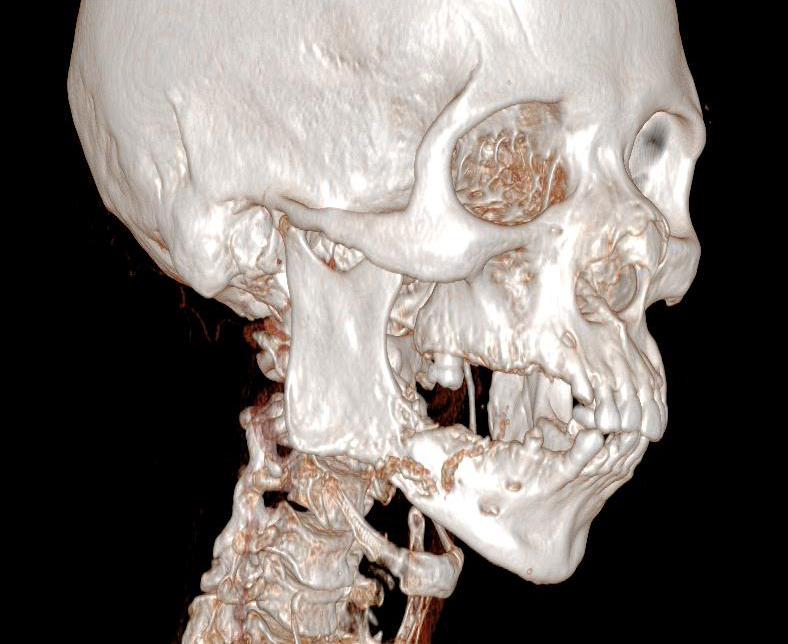

Elle a remarqué, depuis quelques mois, une « boule » en avant de l’oreille à droite, en regard du lobule. Elle n’a pas mal mais est un peu inquiète.

À rechercher devant toute pathologie de la région parotidienne. Un testing musculaire doit être réalisé. Sa présence oriente vers la malignité.

En cas de tumeur maligne, il peut exister des ganglions cervicaux.